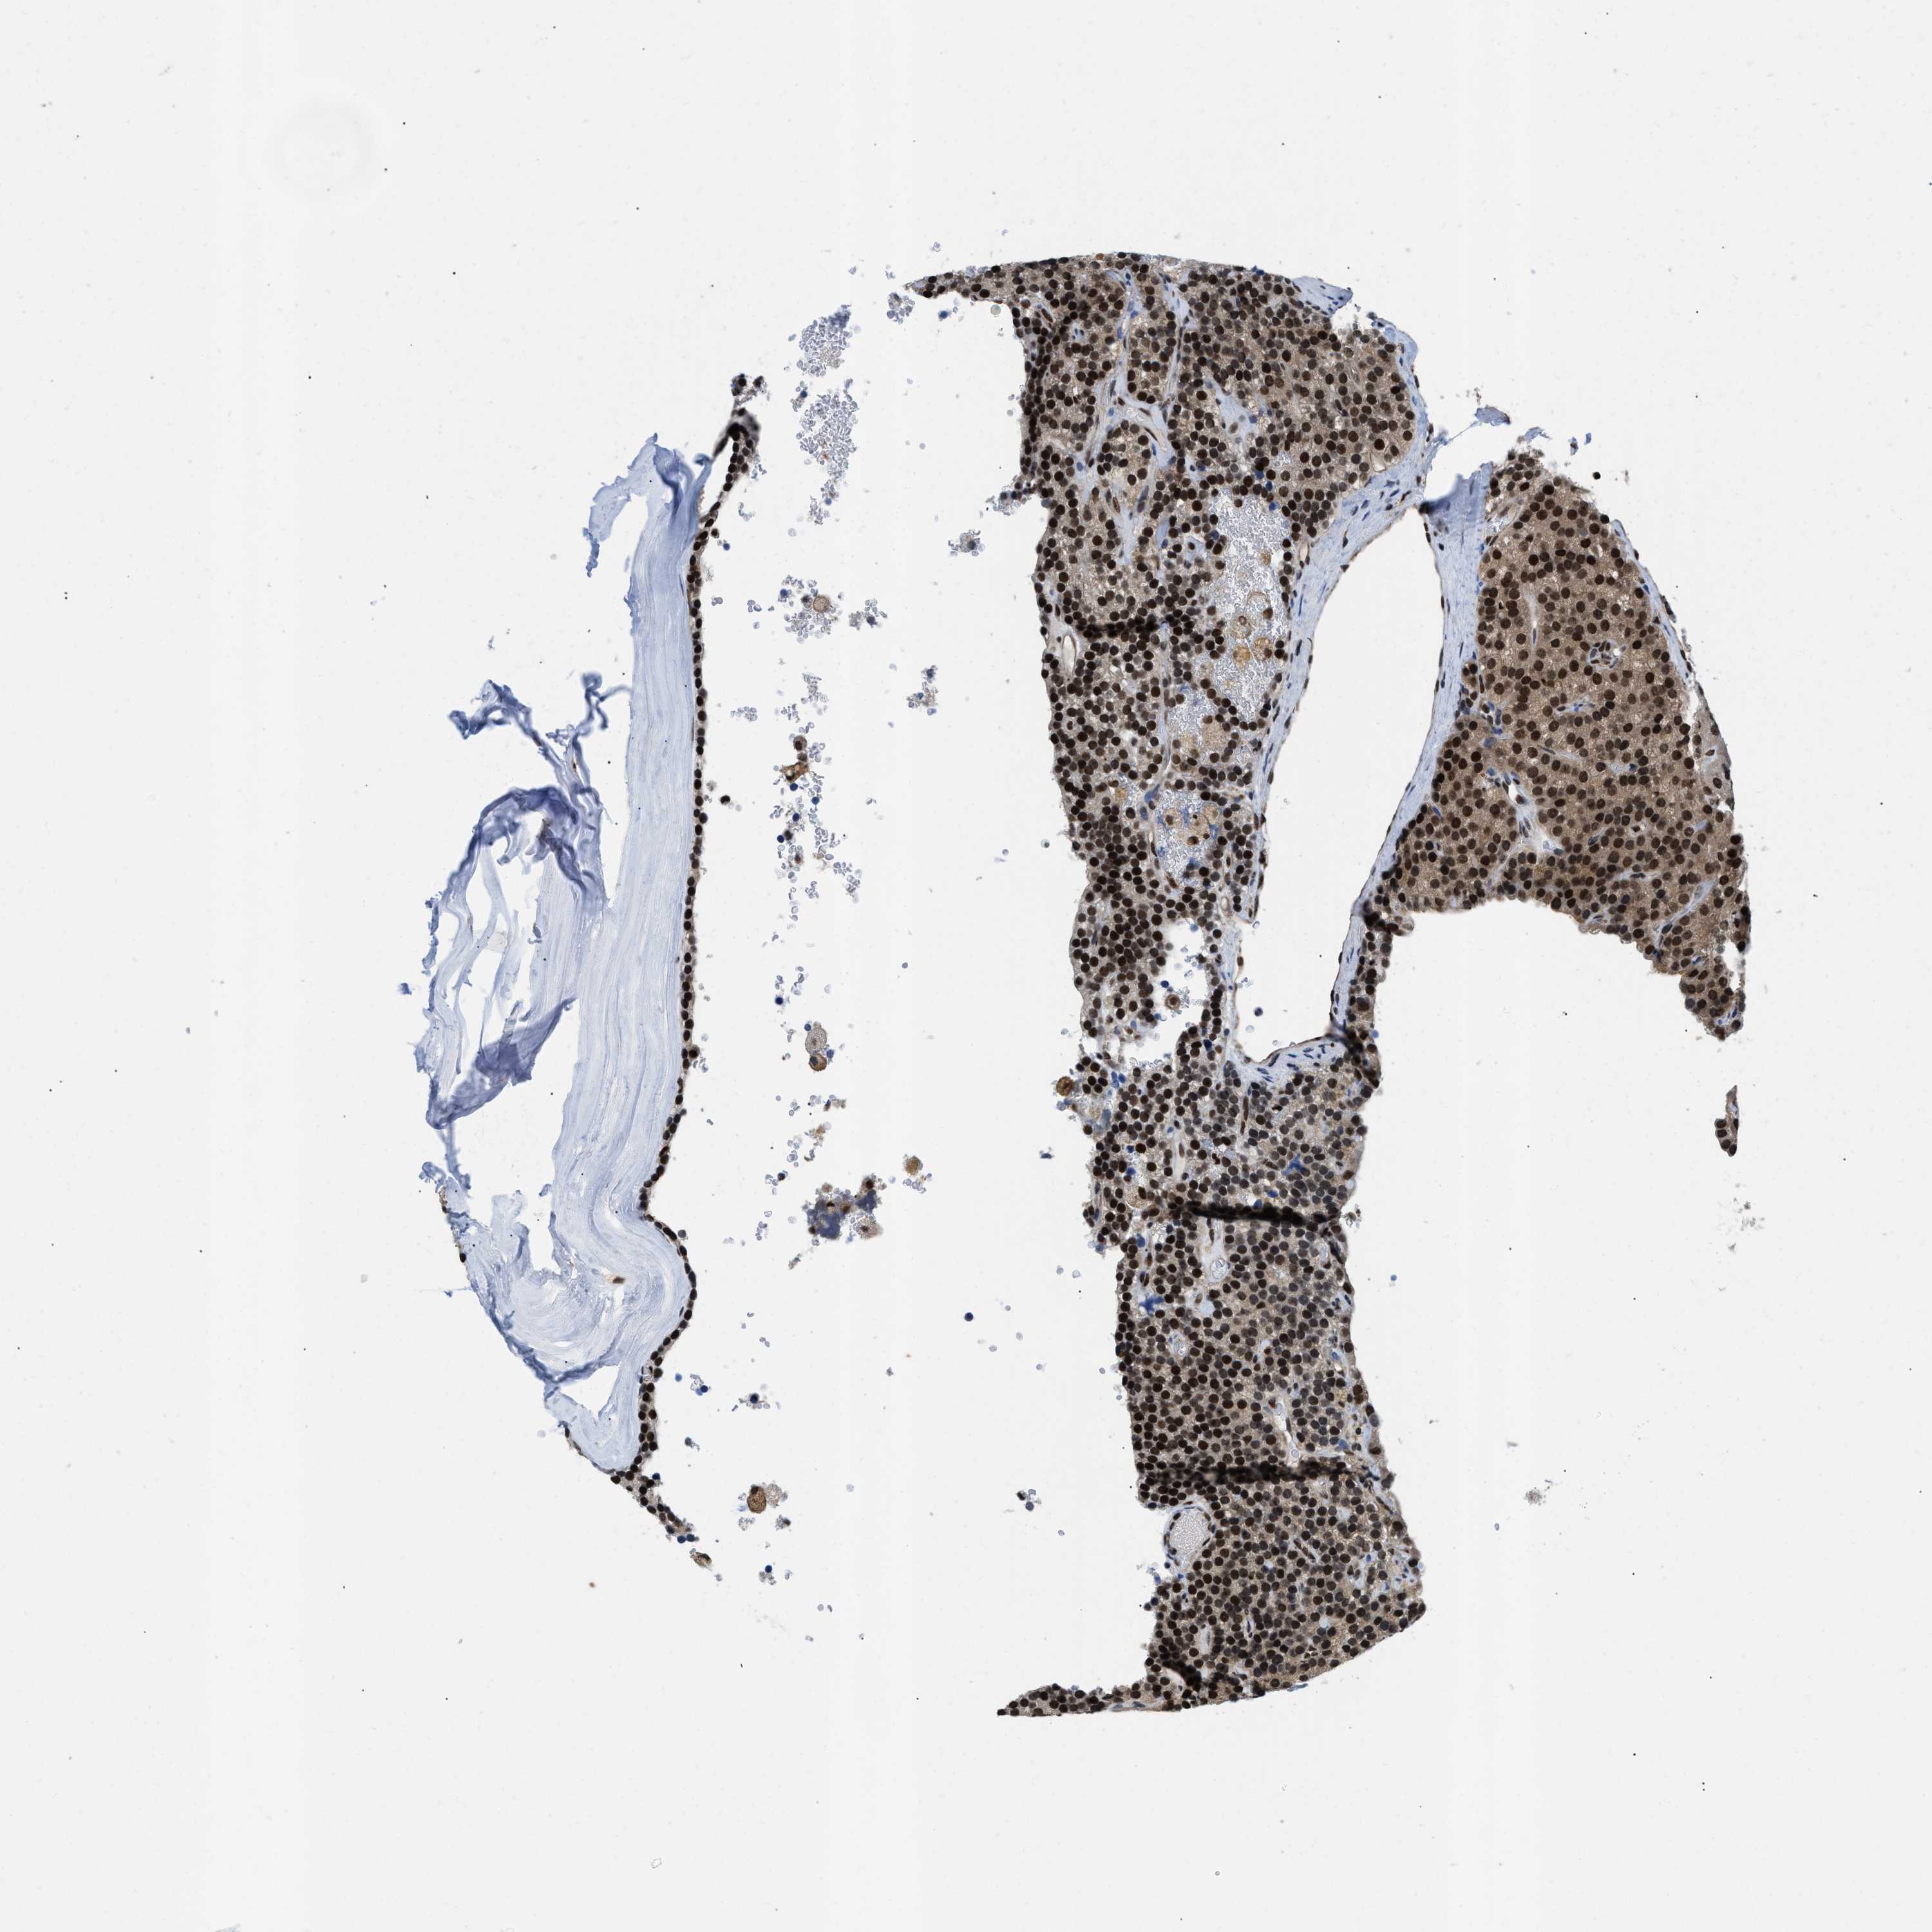

TISSUE PRIMARY DATA PARATHYROID GLAND Show tissue menu

PARATHYROID GLAND - Antibody stainingi

Antibody staining in the annotated cell types in the current human tissue is reported as not detected, low, medium, or high, based on conventional immunohistochemistry profiling in selected tissues. This score is based on the combination of the staining intensity and fraction of stained cells.

Each image is clickable and will lead to virtual microscopy that enables deeper exploration of all samples and also displays staining intensity scores, fraction scores and subcellular localization as well as patient and tissue information for each sample.

Antibody HPA016832Antibody HPA020076Antibody CAB001969

Glandular cells HighHighHigh